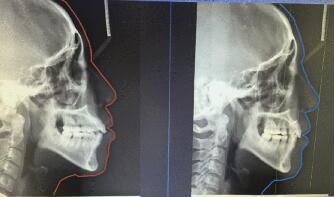

側(ce) 位片

而拍頭顱側(ce) 位片,醫生通常是為(wei) 了測量上下頜骨的畸形程度,通過測量,綜合數據判斷是屬於(yu) 牙性畸形還是頜骨問題,或者說兩(liang) 種情況都有,便於(yu) 確定矯正難易程度和預測矯治結果。